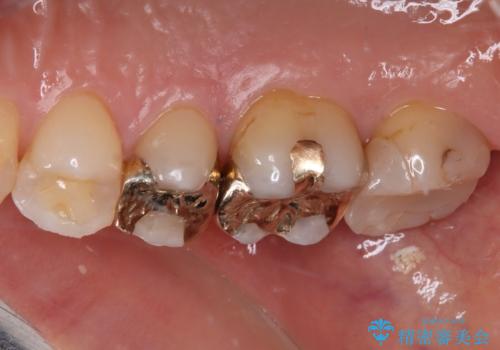

ゴールドは「白い歯」ではありませんが、銀歯の金属色とは異なり、非常にきれいな色合いが特徴です。

もちろん、適合が極めて良いという圧倒的メリットもゴールドクラウンやゴールドインレーの特徴です。